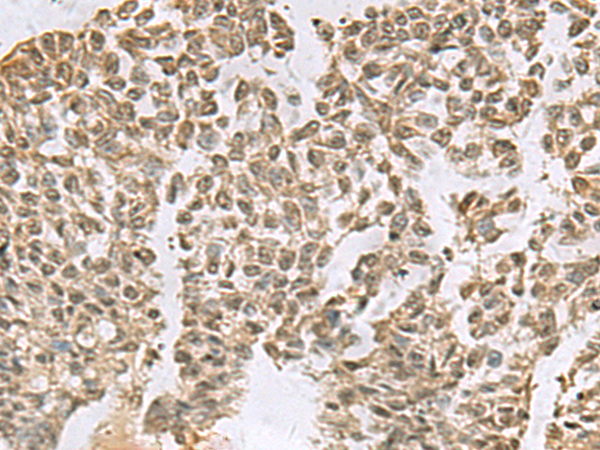

分类: 科研抗体货号: P10213别名: LGP2; RLR-3; D11LGP2; D11lgp2e应用: WB,IHC反应种属: Human, Rat